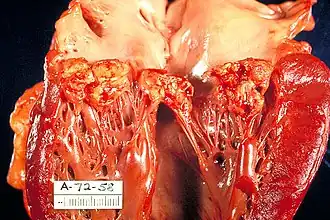

Вегетации митрального клапана при инфекционном эндокардите. | |

Инфекционный эндокардит (ИЭ) — инфекционное полипозно-язвенное воспаление эндокарда, которое сопровождается поражением клапанного аппарата сердца и эндотелия различными патогенными и условно-патогенными возбудителями. Хотя чаще всего в патологический процесс вовлекаются клапаны сердца, он может также проявляться эндартериитом (например, при Коарктации аорты) или развиваться на поверхности инородных тел (центральные венозные катетеры, электроды кардиостимуляторов, сосудистые протезы и др.)[2]. Поражаются в основном митральный и аортальный клапаны, реже - трикуспидальный. Поражение эндокарда правых отделов сердца наиболее характерно для инъекционных наркоманов[3].

Важное условие развития ИЭ — повреждение эндокарда или эндотелия, которое может возникать в результате пороков клапанов, микротравм, операции, проникновения инородных тел и др. К повреждённому эндотелию прикрепляются тромбоциты, образуется небольшой, первоначально стерильный тромб. Затем такой тромб инфицируется различными возбудителями, циркулирующими в крови. Таким образом формируется вегетация, состоящая из бактерий, фибрина, лейкоцитов и тканевого детрита. Вегетация — характерный признак ИЭ, обнаруживаемый при Эхокардиоскопии. Сами бактерии также способны напрямую повреждать клапаны сердца с образованием различных дефектов, фистул и абсцессов.